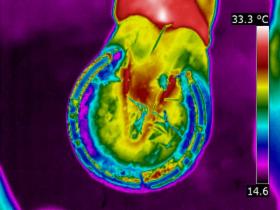

| DISTAL LIMB

| Thermography can point to potential conditions through changes in heat patterns, before the horse shows any clinical signs of injury. It can also reveal hidden signs that other diagnostic tools cannot. It gives us information we didn't know, we didn't know.

| | |  | | | I am very interested in the distal limb and thermography can be used to provide

you and your professional team additional information about conditions such as navicular syndrome,

laminitis, abscesses and corns. Importantly, it can give us information regarding hoof balance and weight-bearing. Hoof balance, often over looked, is a significant influence in the cause of lameness problems not only locally in the foot but throughout the musculature of the body through compensatory issues.